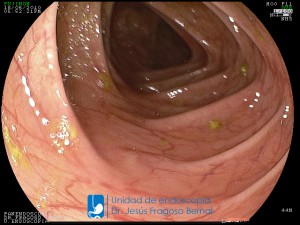

La Unidad de Endoscopía fue creada en 2002 por el Dr. Jesús Fragoso Bernal, es pionera en el estado por la utilización de la tecnología más avanzada, que nos permite ofrecer servicios integrales de diagnóstico y tratamiento para las enfermedades del aparato digestivo.

El profesionalismo de nuestro personal, altamente especializado, se distingue por la calidad y calidez de nuestros servicios con el objetivo de brindar una atención de excelencia en el ambiente más confortable para comodidad y seguridad de nuestros pacientes.

"La Unidad de Endoscopía se ha caracterizado por un progreso continuo desde su inicio marcando la pauta en los procedimientos endoscópicos en el estado de Tlaxcala y estando siempre a la vanguardia tecnológica."

Dr. Jesús Fragoso Bernal